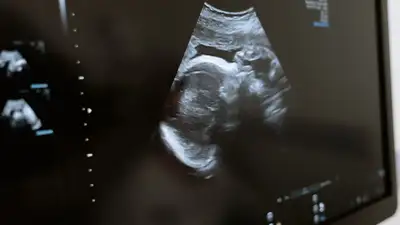

В Казахстане сократилось количество абортов среди девочек-подростков

По данным Бюро национальной статистики, в 2018 году количество сделавших аборт подростков до 15 лет составило 27, а в 2021 году этот показатель уменьшился до 15 случаев, сообщает Zakon.kz.

При этом в бюро отмечают, что число абортов среди подростков более старшего возраста от 15 до 18 лет также сокращается, если в 2020 году было зарегистрировано 1122 случая, то в 2021 году – 1094.

Вместе с тем рождаемость среди девушек-подростков с каждым годом тоже уменьшается и в 2021 году зарегистрировано 23,8 случая на 1 тыс. девушек в возрасте от 15 до 19 лет, что по сравнению с 2015 годом на 7,2 случая меньше.

Если смотреть по регионам, то наибольшая рождаемость среди подростков отмечается в Туркестанской (36,3), Мангистауской (36,2) и Жамбылской (34,3) областях.

Меньше всего рождаемость среди подростков замечена в городах Алматы (11,5) и Астане (12,8).